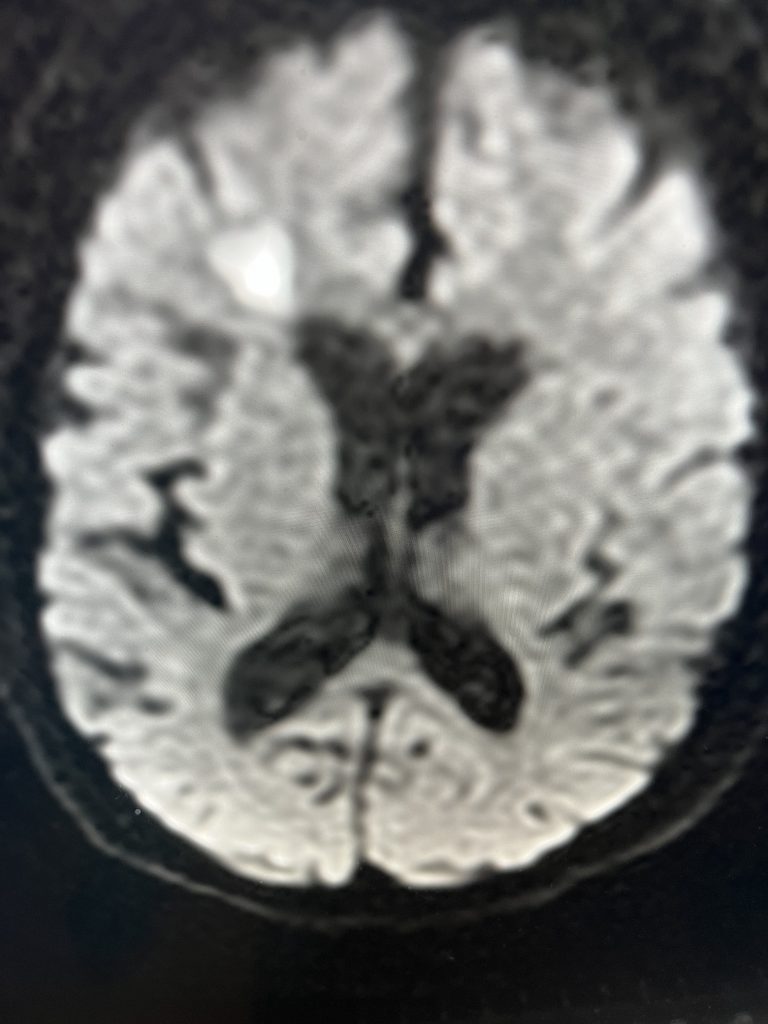

Brain:

Neurosurgeons Collaborate to Treat Giant Symptomatic Meningioma

Author: Ramin Rak M.D., F.A.A.N.S., F.C.N.S., Jonathan L. Brisman M.D., F.A.C.S., Read More!